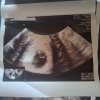

Dziewczyny tak wygląda Moje usg

Pierwsze z5

Drugie z dzis

Wiem że raczej nic z tego nie będzie...

Mam czekać do następnej wizyty .

Wtedy się wszystko wyjaśni

Powinno być już serce bo to 7 ty.

Raczej nastapi poronienie ale twierdzi że ciąża to nie matematyka.

Może w piątek uda mi się dostać do innego ginekologa.

Ciężko określić bo mam nieregularne miesiączki, ostatnia miesiączka 27 luty, więc wypada 7 tydzień, według lekarza to około 5 tydzień, przez to mam przyjść za 2 tygodnie, jutro zrobię Bete.